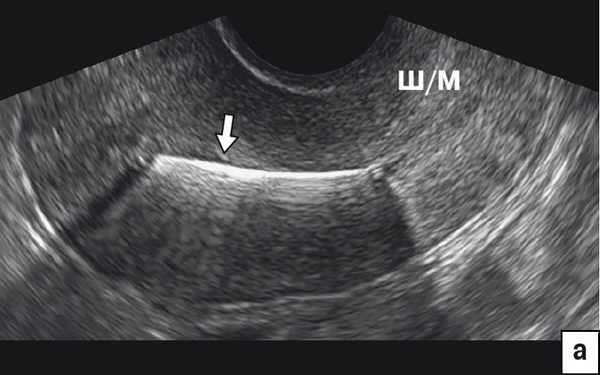

На рис. 2 отражена картина различных ВМС на среднесагиттальном срезе матки при 2D-УЗИ. Для всех Т-образных форм ВМС (включая Мирену) и Multiload стандартной картиной является визуализация гиперэхогенной линейной структуры в проекции полости (рис. 2а). В отличие от Т-образных, Multiload при исследовании в парасагиттальном сечении дает дополнительную специфическую ультразвуковую картину в виде 3-4 продольно расположенных одинаковых гиперэхогенных включений (рис. 2в). Также характерную картину на сагиттальном срезе дают кольцевидные ВМС в виде проксимальной короткой линейной структуры и дистальной отдельной точечной (рис. 2б) и петля Липпеса в виде 4-5 отдельных эхогенных фрагментов (рис. 2г). Кольцевидные ВМС и петля Липпеса в настоящее время практически вышли из употребления.

а) Гиперэхогенная картина стержня ВМС (стрелка) в проекции полости матки.